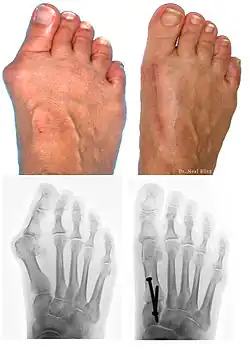

Before and after effects of bunionplasty

At present there are many different bunion surgeries for different effects. The age, health, lifestyle and activity level of the patient may also play a role in the choice of procedure.

Traditional bunion surgery can be performed under local, spinal or general anesthetic. A person who has undergone bunion surgery can expect a 6- to 8-week recovery period during which crutches are usually required to aid mobility. An orthopedic cast is much less common today as newer, more stable procedures and better forms of fixation (stabilizing the bone with screws and other hardware) are used. Hardware may even include absorbable pins that perform their function and are then broken down by the body over the course of months. After recovery long term stiffness or limited range of motion may occur in some patients. Visible or limited scarring may also occur for patients.